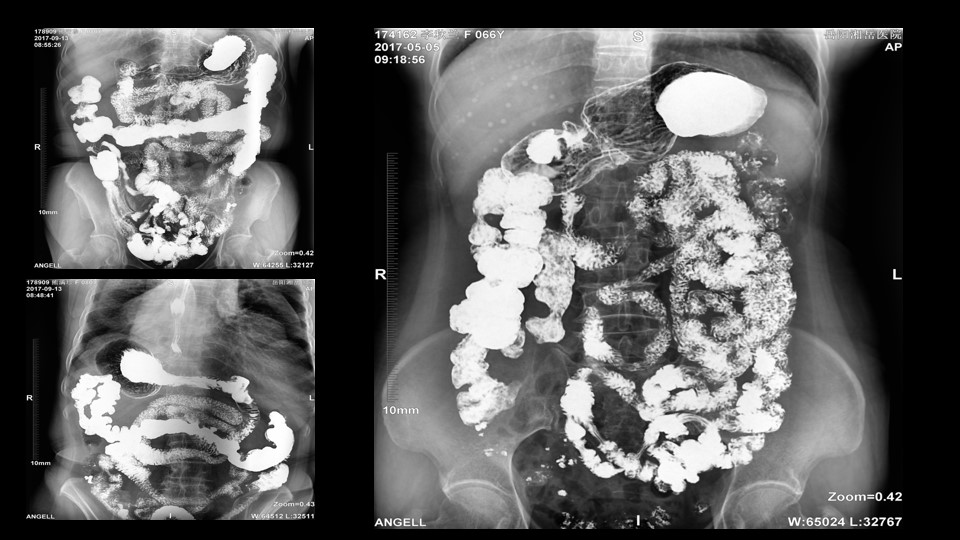

会议开始,岳阳市医学会放射分会副主委、湘岳医院放射科蔡雨主任,结合自身在放射影像的20多年经验,为参会嘉宾分享了动态DR在消化道造影中的应用价值。作为动态DR用户,蔡雨主任结合动态DR的实际拍片与操控经验,分享了动态DR技术在相关群体疾病检查上的独到优势和人文关怀。蔡雨主任说到:“随着内镜技术的发展以及CT、MR的发展,消化道造影在减少,但是这并不意味着消化道造影的价值在下降。以老年人为例,很多老年群体都患有严重的心肺疾病、或者消化道畸形,很多老年人本身就有糖尿病、高血压等等综合疾病,传统内镜的检查对于这类群体来说是一件难以忍受的痛苦,而动态DR的多项创新技术让这类群体的消化系统疾病筛查变得更为人性和精准。任何一个好的消化道造影,一定是患者、诊断医生、临床医生三方满意的结果。388vip太阳集团科技动态DR技术利用900万像素高清拍片、大幅面透视、高清点片、视频保存与回放等核心功能,完全满足临床对消化道气钡双重造影检查的需要。图像质量全面超越以往模拟胃肠机、影增数字胃肠机”。蔡雨主任全面演示了动态DR在食道造影、上消化道造影、小肠双对比造影、结肠气钡双对比造影中的应用,通过动态DR可以清晰获得临床诊断和评估的图像依据。

▲蔡雨主任使用动态造影图像示例